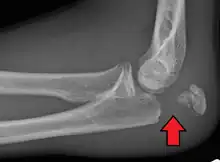

Powerful pull of the triceps muscle can also cause avulsion fractures.

To assess an olecranon fracture, a careful skin exam is performed to ensure there is no open fracture. Then a complete neurological exam of the upper limb should be documented.[5][2] Frontal and lateral X-ray views of the elbow are typically done to investigate the possibility of an olecranon fracture.[1] A true lateral x-ray is essential to determine the fracture pattern, degree of displacement, comminution, and the degree of articular involvement.